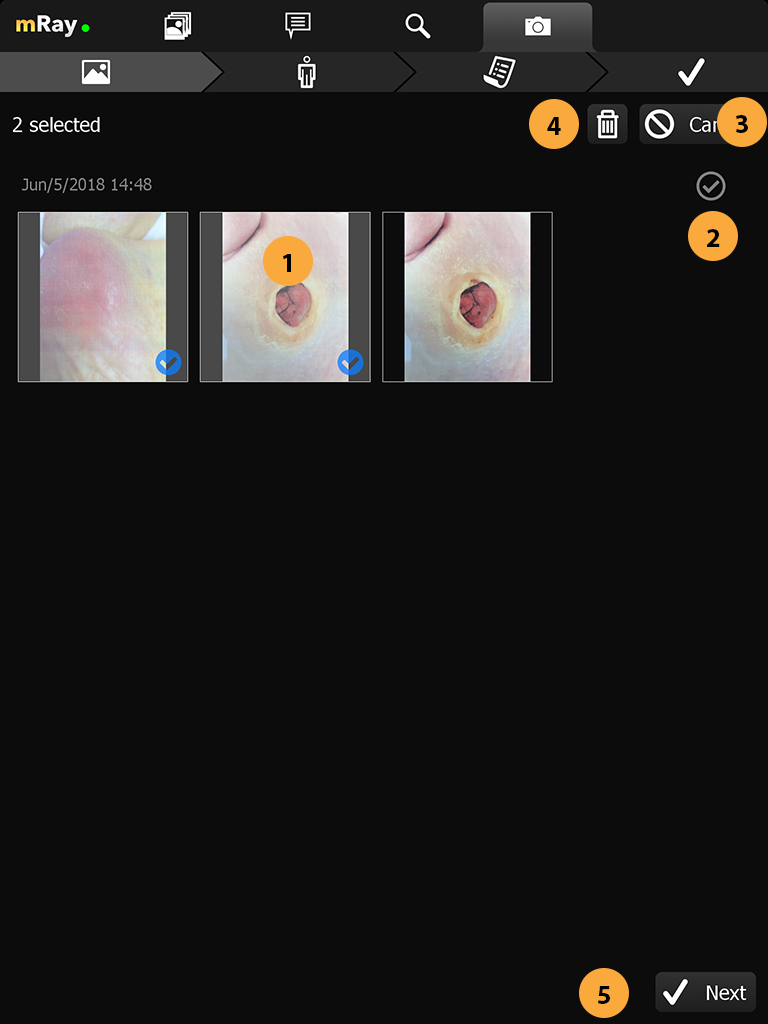

Neue Merkmale über Fotodokumentation Kamera hinzugefügt.

Aufnahme von Bildern zur Wunddokumentation. Versand der Aufnahme als DICOM Datei an ein PACS inkl. aller notwendigen Meta-Informationen